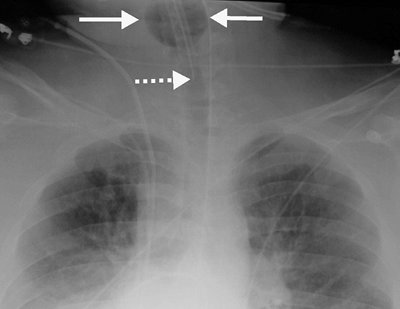

The preferred position of a CVP line tip is central to the venous valves, at the origin of the superior vena cava (SVC). The SVC is formed by the junction of the right and left BCVs. This junction lies to the right of midline at the level of the first intercostal space. The SVC is the preferred location for measuring CVP and avoiding catheter complications. The SVC is joined by the azygos vein posteriorly, just prior to entering the pericardium. Posterior orientation of the catheter tip suggests that it enters the azygos vein (Fig. 5-2).

FIGURE 5-2. Azygos vein placement of central venous catheter. A: PA chest radiograph shows that the catheter tip is positioned over the expected area of the SVC. The tip is seen on end (arrow), however, which is a clue to azygos vein placement. The SVC is joined by the azygos vein posteriorly. B: Lateral chest radiograph shows the catheter coursing posteriorly, along the expected course of the azygos vein (arrows). Note how the more proximal portion of the catheter curves anteriorly (arrowhead), confirming placement from the left.